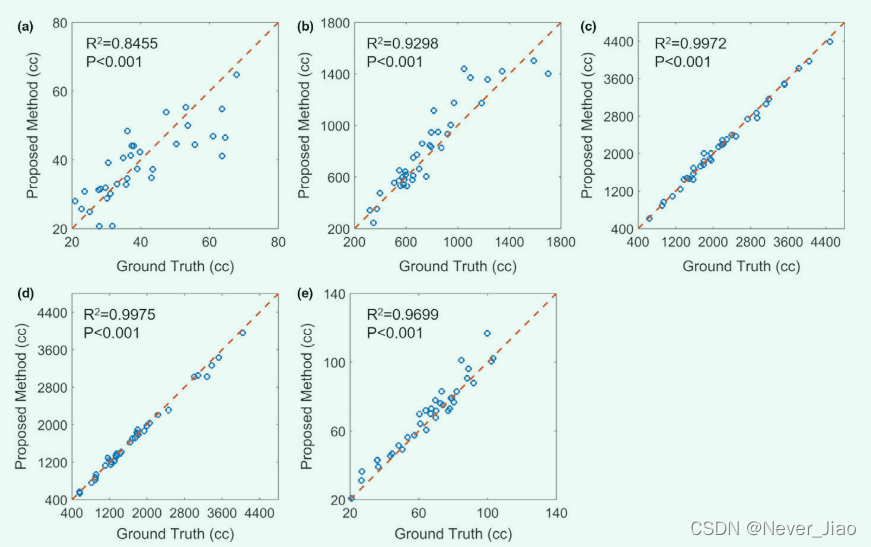

图 6 显示了ground truth与五个 OAR 体积的建议方法之间的线性回归分析。线性相关性 R2 大于 0.84,并且所有 P < 0.001,这表明ground truth体积与使用所提出方法获得的体积之间存在很强的统计相关性。

Fig.6 线性回归分析通过手动轮廓(ground truth)和提议的方法获得的(a)食管,(b)心脏,(c)左肺,(d)右肺,以及(e)脊髓体积。蓝色圆圈表示个体患者的测量,红色虚线表示回归线。